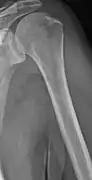

The diagnostic examination of a person with suspected multiple myeloma typically includes a skeletal survey. This is a series of X-rays of the skull, axial skeleton, and proximal long bones. Myeloma activity sometimes appears as "lytic lesions" (with local disappearance of normal bone due to resorption) or as "punched-out lesions" on the skull X-ray ("raindrop skull"). Lesions may also be sclerotic, which is seen as radiodense.[70] Overall, the radiodensity of myeloma is between −30 and 120 Hounsfield units (HU).[71] Magnetic resonance imaging is more sensitive than simple X-rays in the detection of lytic lesions, and may supersede a skeletal survey, especially when vertebral disease is suspected. Occasionally, a CT scan is performed to measure the size of soft-tissue plasmacytomas. Bone scans are typically not of any additional value in the workup of people with myeloma (no new bone formation; lytic lesions not well visualized on bone scan).

Multiple myeloma in the upper arm